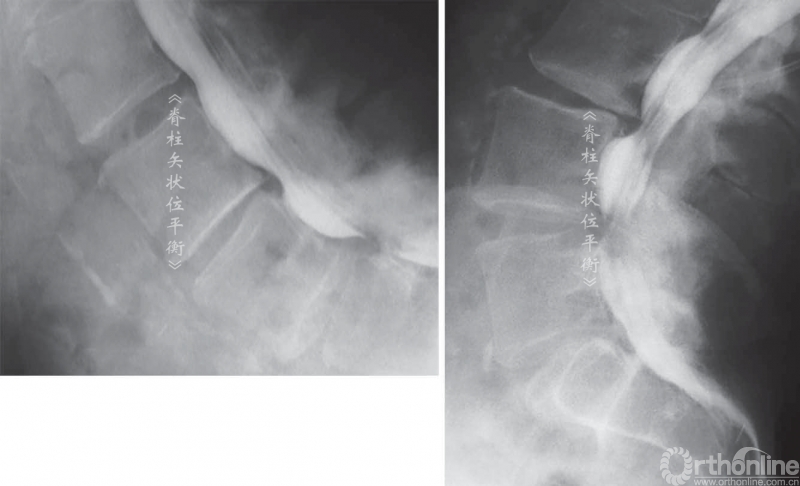

骨关节炎性的椎管狭窄导致伸展时(或前凸)比屈曲时(或后凸)出现更多的症状。不考虑椎管水平因素时,椎管前后径伸展时减小,屈曲时增大。同时,根据神经根的运动原理,神经根屈曲时向椎体前方运动靠近椎体和椎间盘,伸展时向后运动靠近后方椎弓(图8,图9)。

这也解释了颈椎伸展时会加剧压迫性、骨关节炎的颈、臂部的疼痛症状,腰椎屈曲或后凸时可改善腰椎管狭窄引起的神经源性跛行。伸展站立位X线不注射或注射造影剂(脊髓造影术)可证明这种动态受压的过程(图9,图10)。

脊柱后凸会挤压神经引起相应的症状,多见于腰椎管狭窄症。间歇性跛行是继发于椎管狭窄的一种临床症状,在处于伸展位置时加重。一些矢状位失平衡患者可以通过简单的神经根减压术改善其平衡状态。

图9 屈曲(A)和伸展(B)时椎间孔的比较